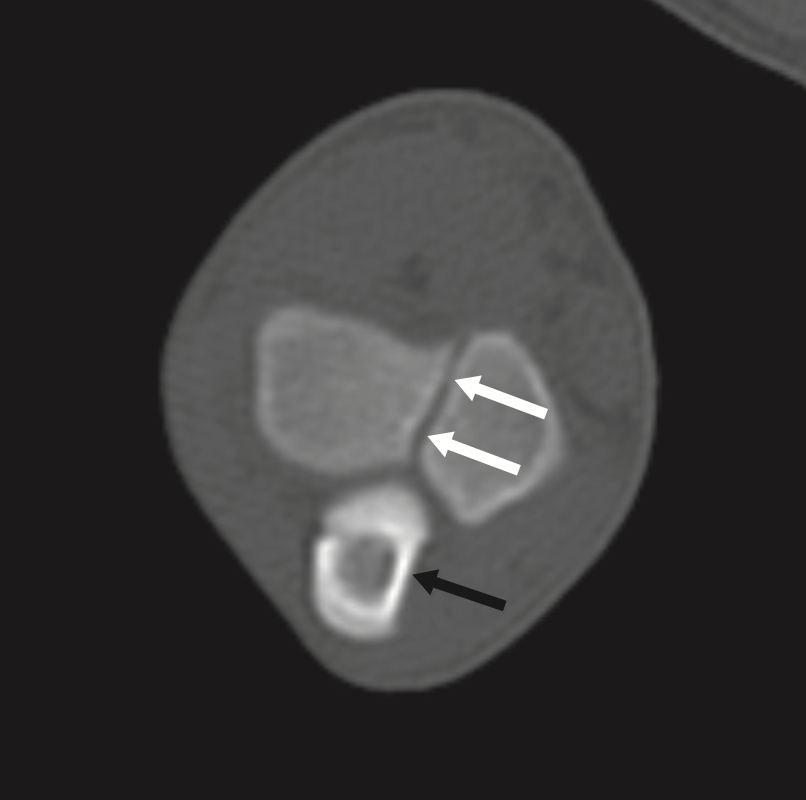

90 day labrador, CT at level of semilunar / trochlear notch. Is this normal or delayed?

A

Incomplete ossification imaging description

l radiolucent line up to 1 mm wide, extending proximally from the trochlear articular sur face to the physeal scar or supratrochlear foramen (50% cases)